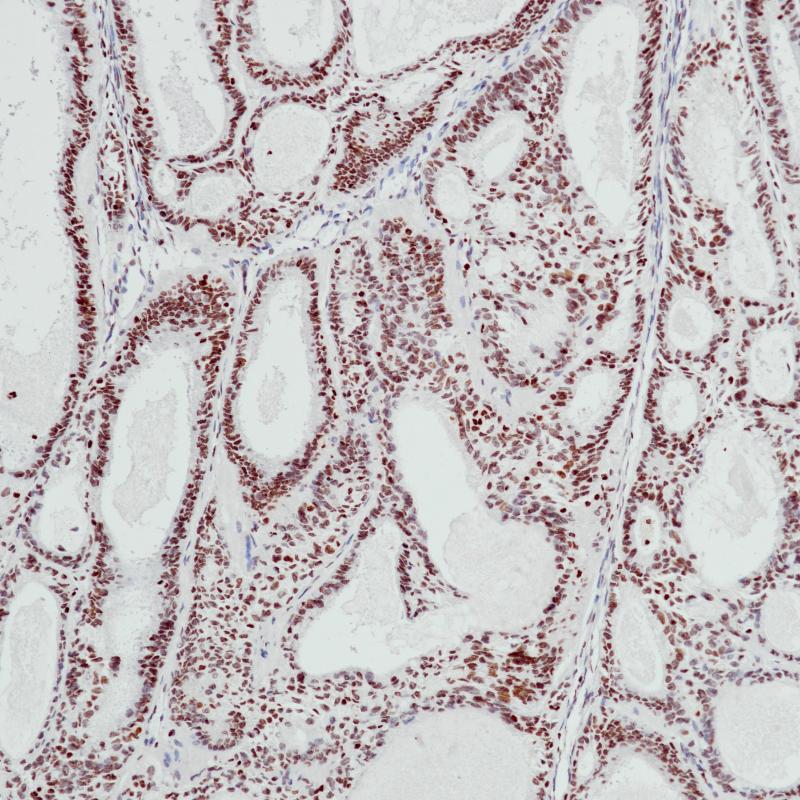

Arginase-1也称作肝型精氨酸酶,它作为尿循环的一个关键酶,在正常肝组织的肝细胞中的表达具有很高的特异性,胆管上皮细胞、肝窦内皮细胞、枯否细胞及血管内皮细胞均不表达。在肝细胞癌诊断中,分化良好及中度分化的肝细胞癌其表达率高达100%和92%,低分化肝细胞癌相对较低,其敏感性高于HepPar1和Glypican3.

细胞质/细胞核